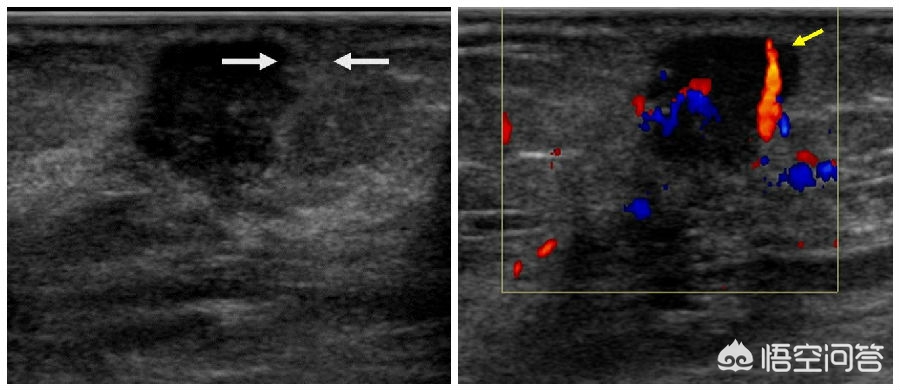

乳腺癌:乳腺癌是女性最常见的恶性肿瘤,在超声下,肿瘤的边界不整,呈锯齿状或蟹足状。内部回声不均,呈低回声区,周边可见毛刺或强回声晕。肿瘤的纵横比大于1,肿瘤内部可见沙粒样钙化(左图箭头)。肿瘤内部血流信号增多,血流形态不规则(右图箭头)。